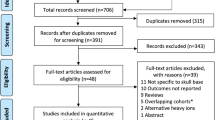

All patients with classic and chondroid skull base chordomas who were treated at the Heidelberg Ion Beam Therapy Center (HIT) between 2009 and 2014 outside the randomized trial were retrospectively included into the analysis. To achieve a definitive demarcation from chondrosarcoma, a test for expression of Brachyury was performed at our center if the samples hadn’t already been tested by the referring hospital [15]. Reference pathology was not obtained routinely.

We aimed to generate a homogenous collective. Therefore, patients with dedifferentiated chordoma were excluded due to their worse prognosis and their small number in the overall collective (total of 3 patients). Patients younger than 18 years or patients who had been previously irradiated to the skull base were also excluded. No further patient selection for the analysis was performed (particularly, no treated patient was excluded from analysis due to comorbidity, high age, or other risk factors).

Herein, we present a retrospective comparison of carbon ion and proton treatments with regards to local control and overall survival. To our knowledge, our cohort represents one of the largest published single-center experiences reporting exclusively chordomas treated solely with particles. Moreover, all tumors were tested for the marker Brachyury to clearly distinguish between chordomas and chondrosarcomas and to exclude the latter [20].

Because of these limitations, combination approaches of photons with particle boosts have been established. The largest cohorts published to date used proton/photon combinations [25, 26], reporting 5‑year LC rates of 73–75%. However, the first study was only presented as an abstract, giving no detailed information, e.g., regarding patient characteristics, while the second study included some patients after complete resection and is therefore difficult to compare. Because of the superior dose distribution of particles compared to photons, several institutions use pure proton or carbon ion treatments instead and observe 5‑year local control rates of 71–92% (including the results of our precursor facility, GSI). In the current study, we found a 5-year local control rate of 64%, which seems slightly inferior, although interstudy comparisons should be interpreted with extreme caution. Concerning this difference, two major points have to be taken into account: except for the exclusion of three patients with dedifferentiated chordomas, no dedicated patient selection concerning inclusion in the analysis (e.g., according to lesion size, adherence or compression to vital structures, comorbidities, or performance status) was performed. Moreover, all tumor specimens were tested for Brachyury, a marker highly specific for chordomas, which nearly eliminates the risk of inadvertent inclusion of chondrosarcomas with a lower risk for local recurrence after particle treatment.

We did not observe a significant difference in local control, overall survival, or toxicity based on the kind of treatment (protons vs. carbon ions). To the best of our knowledge, Iannalfi et al. have published the only prospective data on proton vs. carbon ion treatment of skull base chordomas [27]. They observed 5‑year local control rates of 84% with protons and 71% with carbon ions, but stated that unfavorable patients were specifically allocated to carbon ions. Consequently, the treatment arms were imbalanced with regard to GTV volume, quality of resection, primary versus recurrent disease, and deficits at baseline. Moreover, also patients after macroscopic complete resection were eligible and patients had to be in an adequate performance status. In contrast, all our patients had gross residual disease and no dedicated patient selection in general or regarding the treatment arm was performed. Thus, based on the limited available data, no clear advantage of either protons or carbon ions in the treatment of skull base chordomas can be concluded, at least considering the used dose schedules. In this context, it needs to be mentioned that there are still uncertainties regarding the accuracy of the RBE model (LEM) used for carbon ions [28]. The calculations are based on an RBE of 3–5 for C12 and 1.1 for H1. Especially concerning the newer results of proton therapy, there is a possibility that the estimation of the RBE of C12 may be too high and/or the estimation for H1 too low. Each combination would result in either an underdosing for C12 or an overdosing for H1. This remains subject to discussion and requires further investigation in the future.

Our study has some limitations. As a retrospective single-center experience, some form of bias seems likely. Staging and follow-up procedures were less standardized than in prospective trials, especially regarding distant staging procedures, documentation of side effects, and causes of death. Moreover, efficacy comparisons of proton and carbon ion treatments generally inherit some uncertainties based on the necessarily used assumptions within the dosimetric calculation models (LEM2, RBE). Finally, the current report lacks a specific dosimetric analysis with regard to dose coverage in close proximity to critical organs at risk, which is part of an ongoing project and will be published separately.